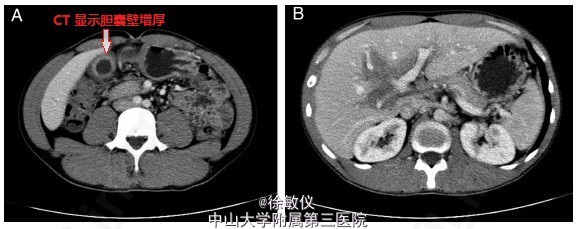

患者,男性,31 岁,主诉:上腹部持续疼痛 3 个月,伴腹泻 1 个月、体重减轻 10kg。胃镜检查发现胃窦部有多处溃疡,PPI治疗 1 个月,未见明显好转,临床症状加重,溃疡面增大。既往有大于 10 年哮喘、湿疹病史。体格检查除了消瘦以及上腹部紧张,其余没有特异性。实验室检查正常,包括大便常规、血清淀粉酶、肝功能、肿瘤标志物、14C- 尿素呼气试验以及寄生虫检测。EGD 检查发现胃窦部有一巨大溃疡,结肠镜发现结肠多发浅表性溃疡(0.2~0.4cm),对比增强 CT 显示胆囊壁增厚,门静脉区域见一无强化的低密度影。血常规嗜酸性粒细胞比例为 59.7%;胃窦部、结肠活检发现大量嗜酸性粒细胞浸润。予强的松(30mg,qd)口服,患者上腹部疼痛、腹泻症状明显减轻,嗜酸性粒细胞计算迅速恢复正常。 1 月后影像学检查发现胃窦部、结肠部溃疡痊愈,胆囊壁恢复正常,门静脉低密度影消失。6 个月后治疗结束,患者恢复正常。最终诊断为嗜酸细胞性胃肠炎。